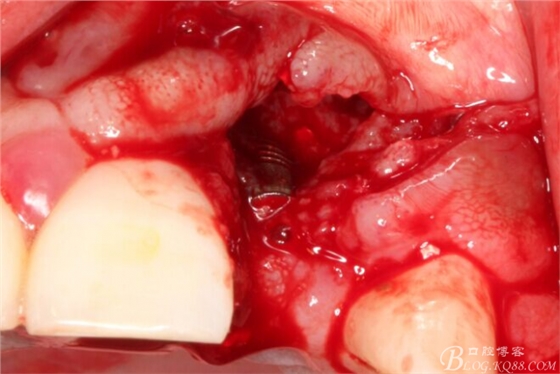

于是我果斷告知患者,手術(shù)失敗了,不能拖延,如不及時(shí)處理,炎癥繼續(xù)發(fā)展會(huì)很快波及鄰牙牙槽骨。患者接受我的建議。切開翻瓣,骨粉及生物膜消失了,骨吸收嚴(yán)重,幸運(yùn)的是,因?yàn)樘幚砑皶r(shí),鄰牙骨支持依然存在。

徹底掻刮。

有老師問我,為什么不在此時(shí)同期植骨同期植入植體?我的觀點(diǎn)是:不要一次做太多事情,做得越多風(fēng)險(xiǎn)越高。再說,此時(shí)軟組織不健康,沒有健康的軟組織如何能保證GBR的成功?所以,我僅放了一塊膠原蛋白就縫上了。